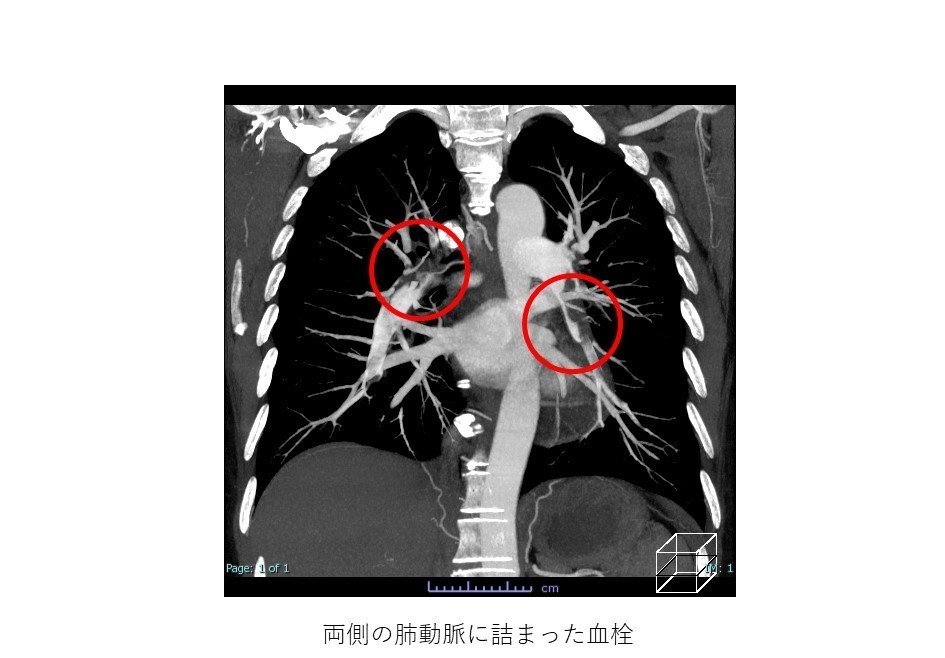

肺塞栓症

これは肺動脈の閉塞を指します。具体的には、血流によって血栓が元の場所から肺に輸送され、肺動脈に詰まります。

肺塞栓症は生命を脅かすものであり、緊急治療が必要です。